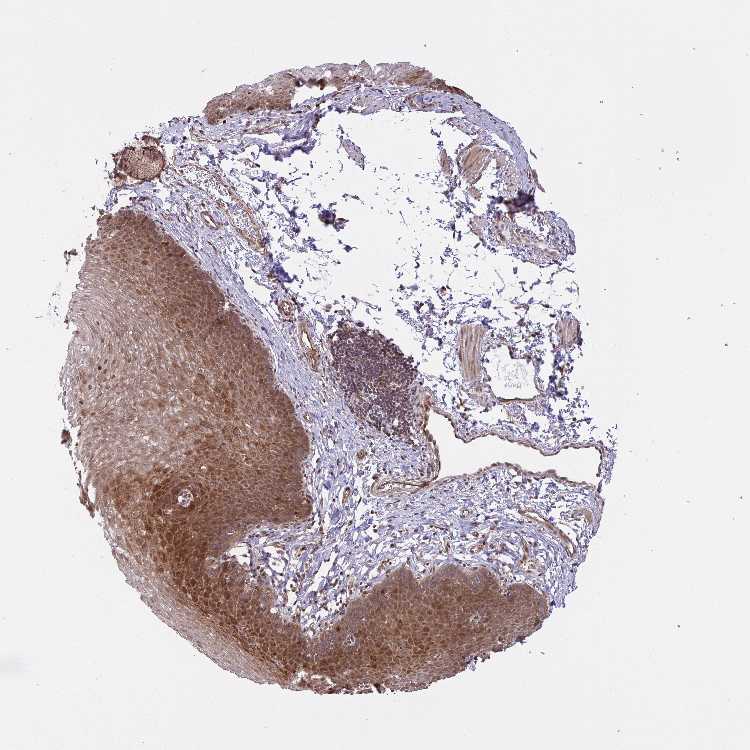

ESOPHAGUS - Antibody stainingi

Antibody staining in the annotated cell types in the current human tissue is reported as not detected, low, medium, or high, based on conventional immunohistochemistry profiling in selected tissues. This score is based on the combination of the staining intensity and fraction of stained cells.

Each image is clickable and will lead to virtual microscopy that enables deeper exploration of all samples and also displays staining intensity scores, fraction scores and subcellular localization as well as patient and tissue information for each sample.

Antibody HPA055548Antibody HPA056074Antibody CAB033838

Squamous epithelial cells HighNot detectedMedium